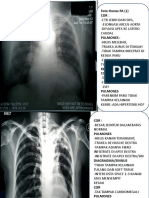

YTH TS :

Hasil pemeriksaan Thorax PA:

- Corakan bronchovascular tampak prominent

- Cor : kesan membesar, aorta dilatasi, elongasi dan kalsifikasi

- Kedua sinus dan diafragma baik

- Tulang-tulang intak

- Tampak bayangan opaq dengan ukuran +/- 3 x 1,5 cm pada regio colli dextra (kalsifikasi pada

thyroid)

Kesan :

- Bronchitis

- Cardiomegaly disertai dilatatio, elongatio et atherosclerosis aorta